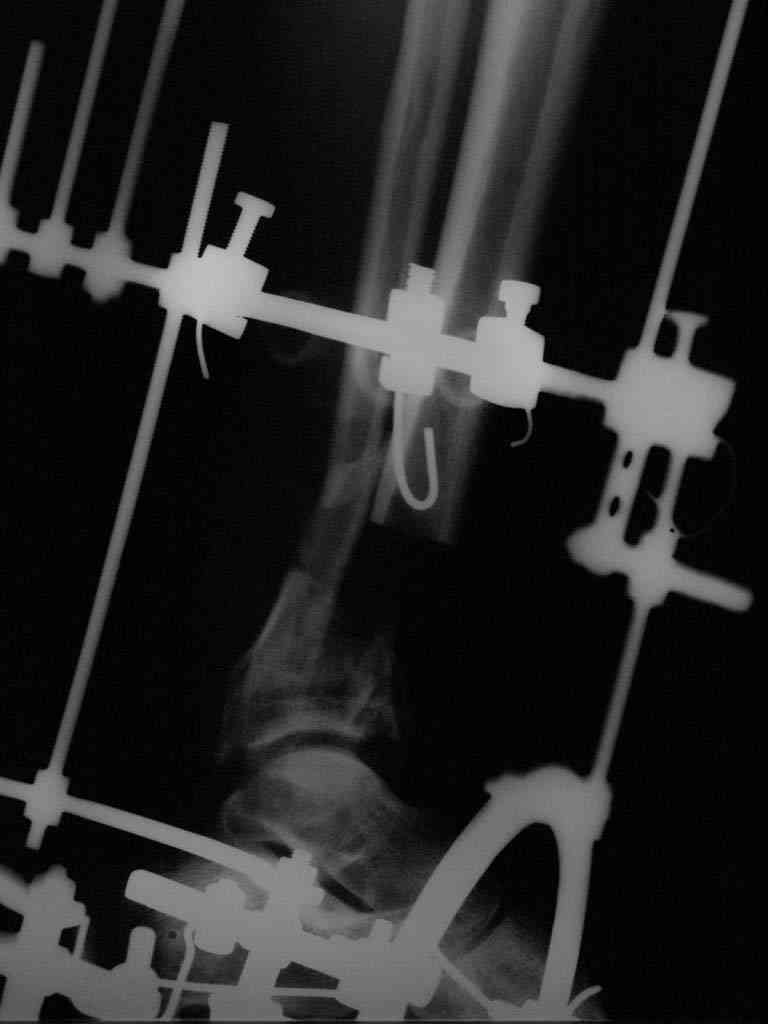

|  |  |  |  status localis на 14.11.08 (В ране визуализируется сухожилие.) | Больной А, 40 лет, находится в клинике с 15.10.08 с диагнозом: Сочетанная травма. Ушиб головного мозга лёгкой степени тяжести. Компрессионные переломы тел 12 грудного и 5 поясничного позвонков без неврологических осложнений. Закрытый внутрисуставной многооскольчатый перелом дистальных метаэпифизов обеих костей правой голени со смещением. Открытый внутрисуставной многооскольчатый перелом дистальных метаэпифизов обеих костей левой голени со смещением (см. Р-граммы). Хронический алкоголизм. Доставлен СМП после падения с 5-го этажа (не суицид). При поступлении состояние тяжелое. Глубокое оглушение. Дыхание самостоятельное, адекватное. Гемодинамика стабильная. По внутренней поверхности левой голени, в нижней трети, рвано-ушибленная рана 10-6 см, из раны выстоит проксимальный отломок большеберцовой кости, рана обильно загрязнена землёй. Интенсивная терапия в условиях реанимационного отделения, вытяжение за правую пяточную кость, параартериальная блокада обеих нижних конечностей, гипсовая лонгета на левую нижнюю конечность, ас-повязка на рану. Через 4 часа после поступления оперирован: после неоднократного промывания раны тёплой проточной водой с мылом, антисептиками, при ревизии определяется земля в канале проксимального отломка на глубину 3 см..., отсутствие надкостницы на концах дистального и проксимального отломков на 3 см. Удалено значительное количество мелких костных фрагментов, перемешанных с землёй, выполнена ПХО раны, резекция проксимального конца большеберцовой кости на 3,5 см, ЧКДО аппаратом Илизарова. Рана не ушивалась. В последующем перевязки раны с "Левомеколь", через 3 недели с момента травмы в ране определялись грануляции, нежизнеспособный конец дистального отломка. 10.11.08 ВХО раны, резекция дистального отломка на 3 см, перемонтаж аппарата наружной фиксации (см. Р-граммы). Отломки сближены на 2 см (остеотомию малоберцовой не делали). В настоящее время (5 сутки после операции) незначительное количество серозного отделяемого из раны, имеется дефект кости 4 см (см. Р-граммы). В последующем склоняемся к перемонтажу аппарата наружной фиксации, остеотомии малоберцовой кости в области повреждения, сближении отломков. По заживлению раны удлинение левой голени на 4 см. Однако, некоторыми высказывалось мнение о необходимости артродеза. Представляем рентгенограммы левой голени при поступлении, после повторного оперативного лечения и фото st.localis на 14.11.08. Будем очень благодарны за критику, комментарии, пожелания и мнения о дальнейшей тактике лечения.